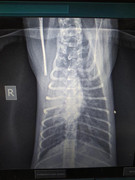

Вчера Шанелька была у Кравченко, и он конечно направил ее на МРТ. В Минске сейчас МРТ не работает, поэтому поехали на КТ в клинику сасов. Мы были очень оптимистично настроены, потому что у нее есть глубокая болевая чувствительность.

Результаты КТ расстроили sad  Перелом позвоночника и пневмония. Она немного кашляла, но Настя это списала на глисты. Настя ей в первый день дала Милпразон и глисты выходят до сих пор. Конечно, о воспалении легких даже не подозревали.

Сегодня утром снова были у Кравченко. Он пояснил, что по результатам КТ у нее перелом 13-го позвонка, который находится в грудной области. Но ее проблема, из-за которой есть паралич лап, находится в районе крестца. На КТ там повреждений нет. Поэтому нам все равно придется делать МРТ sad   Сейчас все очень осложняет пневмония, пока ее не вылечим наркозить больше нельзя. По большому счету делать КТ было тоже очень опасно, но кто знал.. Назначили юнидокс. Я сталкивалась с пневмонией у котов ранее, но юнидоксом не помню, чтобы ее лечили. Может нужно что-то сильнее?

Шанель в стационаре. Сегодня поднялась температура, Курзина направила на снимок - пневмония уже двусторонняя sad

Сегодня был контрольный рентген. Улучшения есть, но не такие, какие хотелось бы видеть после курса двух антибиотиков. Сегодня врач рентгенолог предположил, что у Шанельки помимо всего прочего грибковая пневмония.

У Шанельки все хорошо. Сделали повторные снимки, лечение работает, но не так быстро как хотелось бы. Плюс ко всему прочему нашли микру. Лечимся.